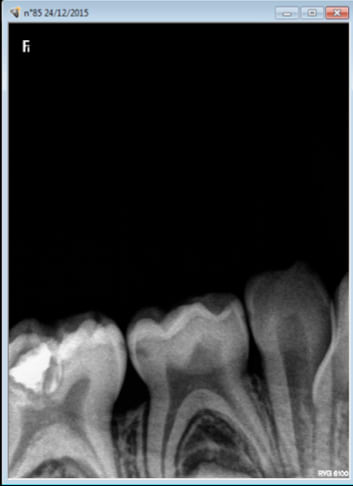

Mais je t'invite à grouper les soins sur la teigne de 7 ans que j'ai eu en urgence pour mon cadeau de Noel professionnel hier : pulpite sur 85 ( merci quick sleeper) pour cause de composite défectueux ( et ne me demandes pas pourquoi le confrère a fait cette bouse sans anesthésie sur la teigne).

J'ai cru apercevoir une parulie sur la 75 ( ou la 74 pas eu le temps de de préciser laquelle dans le feu de l'action) et il doit y avoir d'autres soins à reprendre ailleurs.